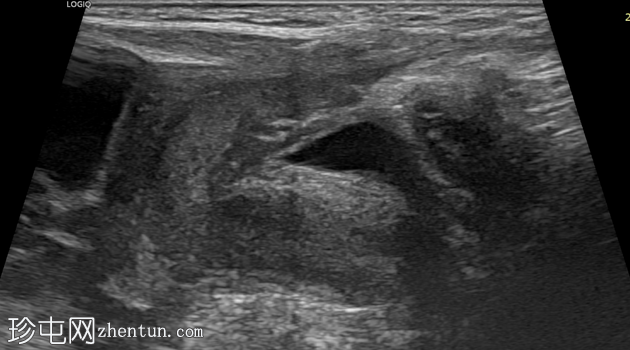

右侧努克氏疝管长约6毫米,内含部分子宫和卵巢(大小约1.5 x 1厘米)。在整个检查过程中,这些组织均保持原位。

对侧附件呈多囊性改变,大小约3 x 1.8厘米。

上述超声特征清晰地显示了努克氏疝管的内容物及其延伸范围;其中包含患者的一侧卵巢和部分子宫组织。

这些特征符合卵巢努克氏疝的诊断。